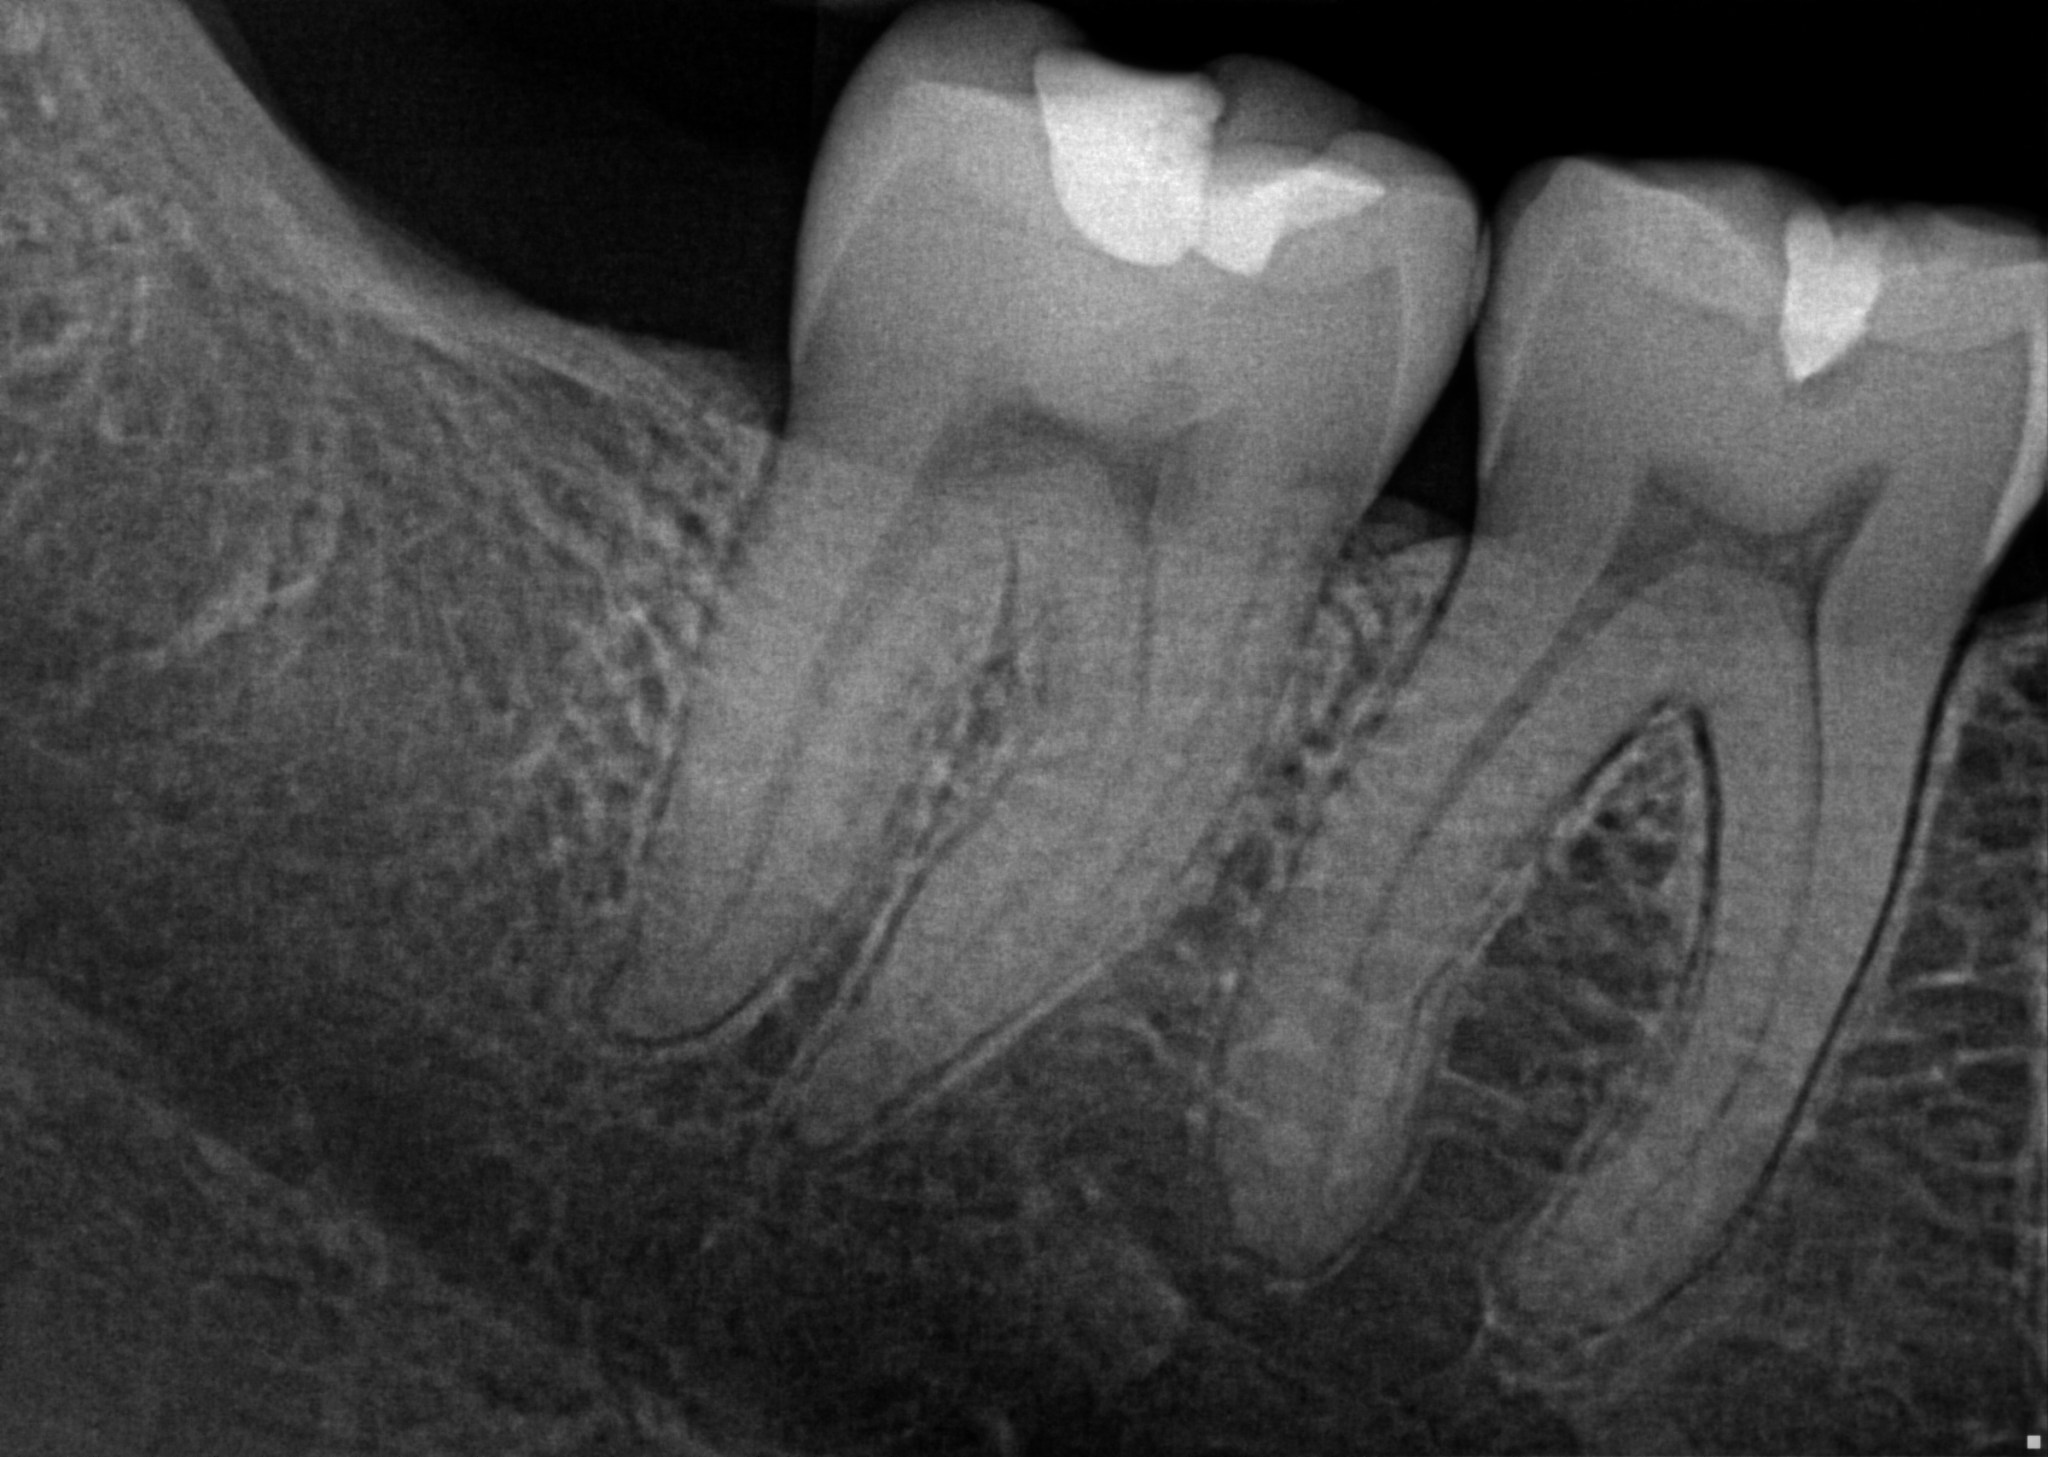

For the patient, digital X-rays mean lower radiation exposure and images that can be manipulated for more accurate diagnoses and to communicate problems to the patient, Mandelkern says. “That translates directly to better diagnosis and treatment for the patient.”